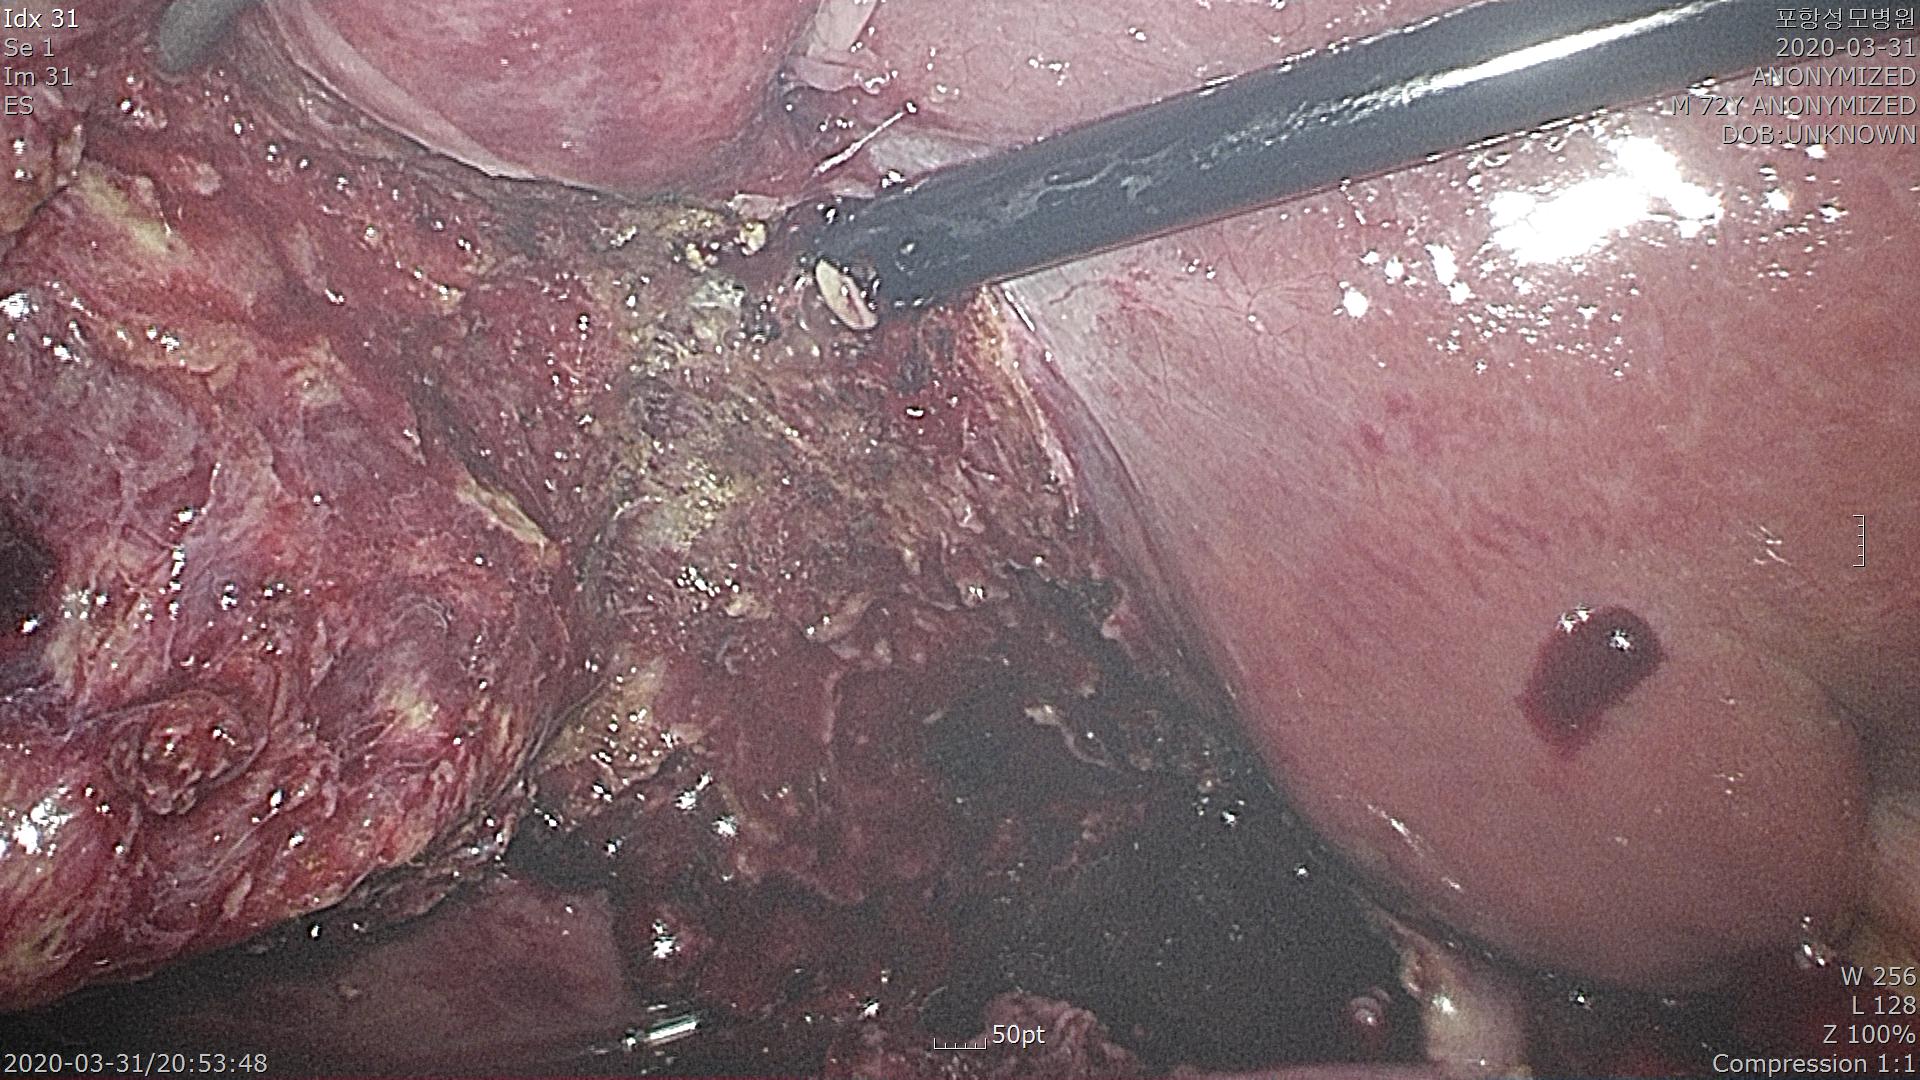

담낭관을 결찰하고 간후벽에 붙어 있는 담낭 전체를 박리합니다.

간은 전부 혈관 덩어리라 출혈이 많습니다.

간에서 담낭이 제거되기 직전 사진입니다.